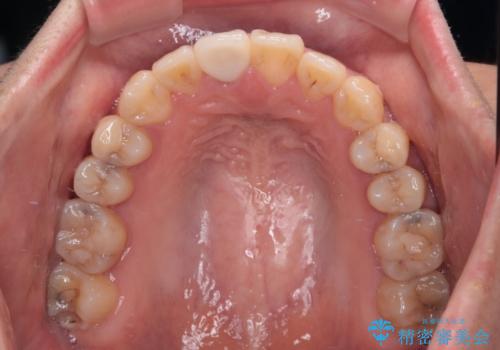

治療開始直後に上顎前歯に激しい痛みが発現し、矯正治療を休んだり、マウスピースの装着時間を短くしたりと工夫をしましたが、残念ながら治療途中で失活していることが分かりました。

矯正治療の途中で前歯の根管治療とオールセラミッククラウンによる補綴治療を行い、その後インビザライン1セットを用いて細かい部分を仕上げました。